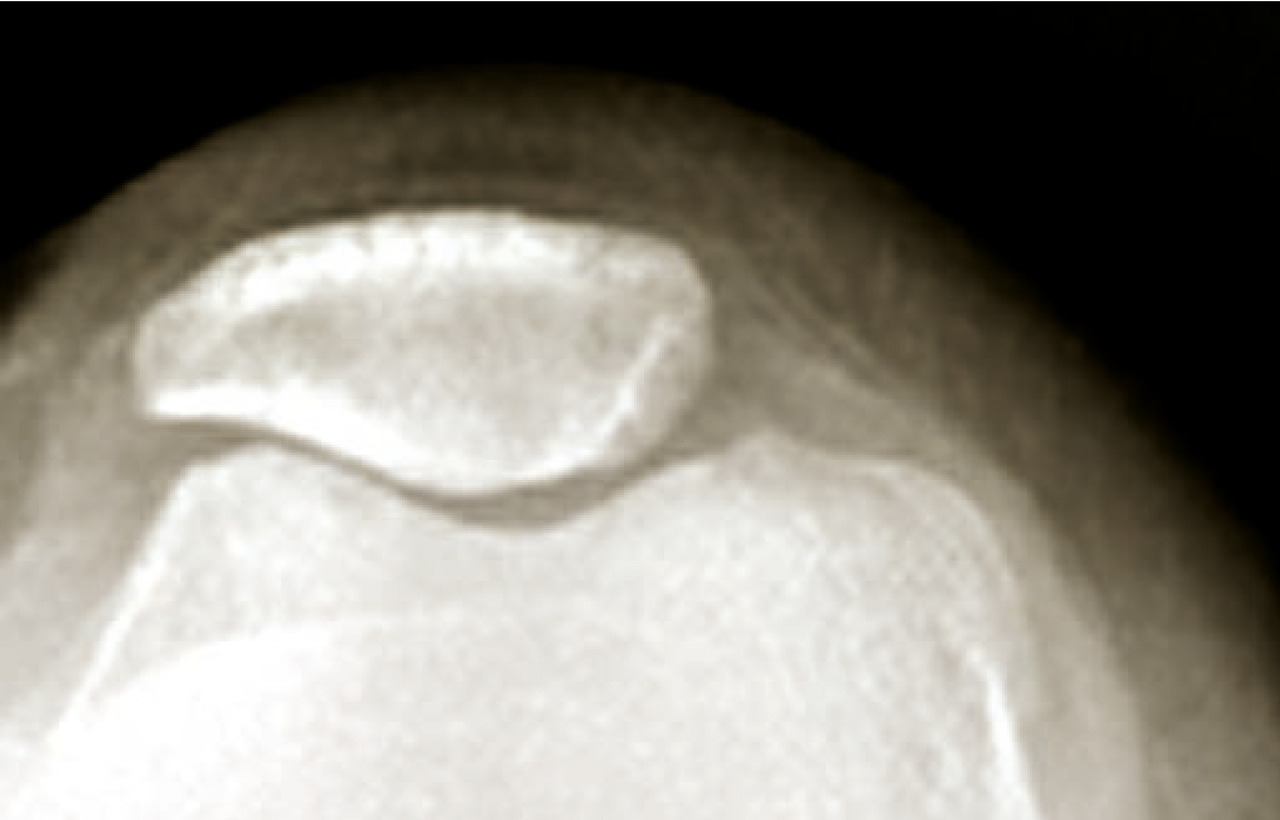

Arthrose de l’épaule (omarthrose)

C’est l’arthrose de l’articulation gléno-humérale. Elle est presque toujours secondaire. On distingue les omarthroses :

• centrées, qui sont primitives ou secondaires à une fracture, une arthrite ou une ostéonécrose (fig. 9) ;

• excentrées, qui sont le plus souvent secondaires à une rupture de la coiffe des rotateurs de l’épaule (fig. 10).

L’omarthrose centrée se manifeste par une ostéophytose céphalique humérale, un espace sous-acromial respecté, un pincement tardif de l’interligne gléno-huméral. Une évolution vers une excentration antéropostérieure avec une subluxation postérieure peut aussi s’observer.

L’omarthrose excentrée se définit par un pincement de l’espace sous-acromial, une arthropathie sous-acromiale avec remodelage du tubercule majeur. Elle peut se compliquer par la constitution d’une néo-­articulation acromio-humérale et une chondrolyse gléno-humérale.